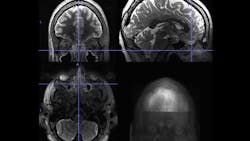

The researchers identified a study cohort from the Human Connectome Project, an open-access, brain-focused dataset of 1,206 healthy adults ages 22-35. Data included radiology image scans and cognitive/behavioral measurements. The scans enabled them to identify 22 people with moderate or severe sinus inflammation as well as an age- and gender-matched control group of 22 with no sinus inflammation. Functional MRI (fMRI) scans, which detect cerebral blood flow and neuronal activity, showed these distinguishing features in the study subjects:

· Decreased functional connectivity in the frontoparietal network, a regional hub for executive function, maintaining attention and problem solving

· Increased functional connectivity to two nodes in the default-mode network, which influences self-reference and is active during wakeful rest and mind wandering

· Decreased functional connectivity in the salience network, which is involved in detecting and integrating external stimuli, communication and social behavior